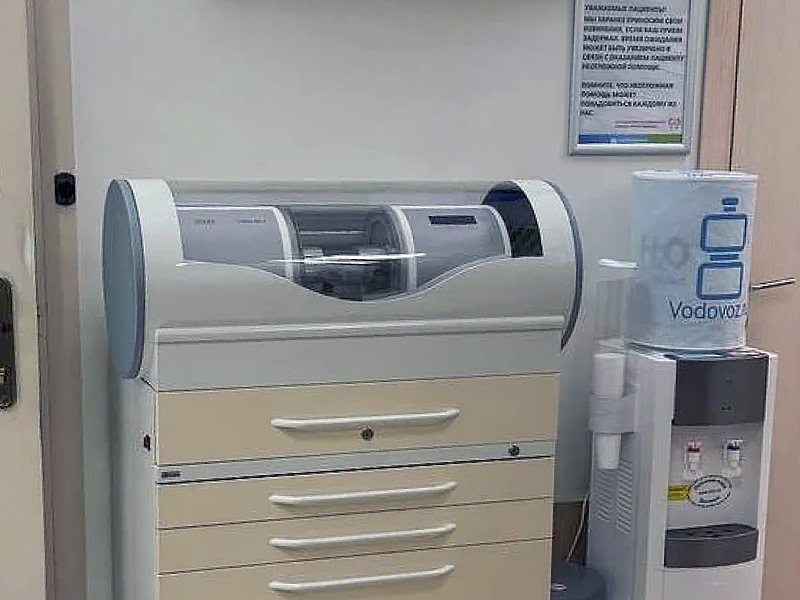

Наше оборудование

Восстановление зуба коронкой Cerec из Empress в клинике (без слепков)

Восстановление зуба коронкой Cerec из Emax в клинике (без слепков)